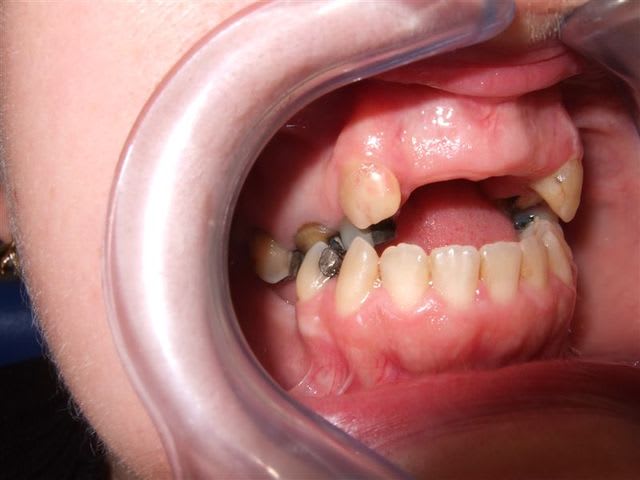

- patiente qui se plaint de douleurs mol inf et pb articulaires : cf empreintes et pano

- extraction 47/37 avec entre temps foyer infectieux sur 26 qui se manifeste : dépose cc et tentative RTE : très mauvais pronostic car résine phénoplaste qui au premier abord ne se laisse pas faire.

- patiente qui veut le trt le plus simple qui soit, en évitant toute forme de chirurgie sauf si vraiment indispensable, critère esthétique non retenu avec une bonne tolérance pour prothèse amovible.